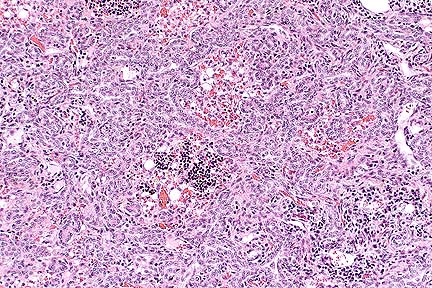

Florid biliary proliferation within portal areas and multifocal aggreates of medium numbers of lymphocytes in a cat with lymphocytic cholangiohepatitis. (HE, 100X, 83K)

Contributor's Diagnosis and Comments: Liver: Cholangiohepatitis, lymphoplasmacytic, chronic, periportal, diffuse and bridging, with nodular hyperplasia and marked bile duct proliferation, Domestic Shorthair cat, feline.

Feline cholangitis/cholangiohepatitis syndrome occurs in three histologic forms: suppurative cholangitis/cholangiohepatitis, long-term nonsuppurative cholangitis/cholangiohepatitis, and biliary cirrhosis. The three forms are thought to be progressive stages of the same disease. Initial inflammation of the biliary system spreads to the adjacent hepatic parenchyma. The long-term result is portal fibrosis and biliary hyperplasia. The etiology of the disease is unknown, although immune-mediated mechanisms have been proposed. Additionally, bacterial and parasitic infections (including toxoplasmosis) have been associated with suppurative cholangitis. Many cats with the disease respond favorably to corticosteroid and/or antibiotic therapy. Biochemical findings vary. Aspartate aminotransferase, alanine aminotransferase, and alkaline phosphatase enzymes are often high in the suppurative form, but can become normal as the disease progresses. Hyperbilirubinemia is common. In the present case, a causal relationship was not established between the toxoplasmosis and liver lesions.

AFIP Diagnosis: Liver: Biliary hyperplasia and fibrosis, bridging, diffuse, marked, with hepatocellular loss, nodular regeneration, and lymphoplasmacytic and neutrophilic cholangiohepatitis, Domestic Shorthair, feline.

Conference Note: Although the three histologic forms of feline cholangiohepatitis syndrome (suppurative, non-suppurative, and biliary cirrhosis) may represent a progression of lesions of the same cause, there are some inconsistancies with this theory. For example, while it might be assumed that the nonsuppurative form is a more chronic stage of the suppurative form, the nonsuppurative lesion seems to occur in a generally younger group of cats than the suppurative form.

Suppurative cholangitis/cholangiohepatitis is characterized by portal and parenchymal infiltration of neutrophils, accompanied by mild fibrosis and bile duct hyperplasia. Suppurative cholangiohepatitis is most common in middle-aged to old cats. Enteric bacteria are frequently isolated from these lesions and ascending bacterial infection of the bile duct has been proposed as the etiology; however, cholelithiasis, trematodes, the nephrotic syndrome, and protozoa have also been associated with suppurative cholangiohepatitis.

Nonsuppurative cholangiohepatitis is characterized by portal infiltrates of plasma cells and lymphocytes, bile duct hyperplasia, and periportal fibrosis; small numbers of neutrophils may be present. Nonsuppurative cholangiohepatitis has also been associated with pancreatitis. Cats less than 4 years of age are primarily affected.

Biliary cirrhosis is presumed to result from progressive cholangiohepatitis; however, the etiology is unknown. Histologically, there is prominent bridging portal fibrosis, bile duct hyperplasia, nodular hyperplasia, and chronic inflammation of varying severity. Regardless of etiology, the prognosis for any form of cholangiohepatitis is guarded due to a generally poor response to therapy.

Some attending the conference diagnosed cholangiocarcinoma; however, there are several features that argue against a neoplastic process. At the center of most of the areas of bile duct hyperplasia, there are pre-existent portal structures, suggesting a diffuse proliferative lesion rather than widespread portal invasion of neoplastic cells. Additionally, there is little cellular atypia of the proliferating epithelial cells, the proliferating ducts are linedby a single layer of cells, and the mitotic rate is low. Also, nodular hepatocellular regeneration and biliary hyperplasia are not commonly associated with cholangiocarcinoma.